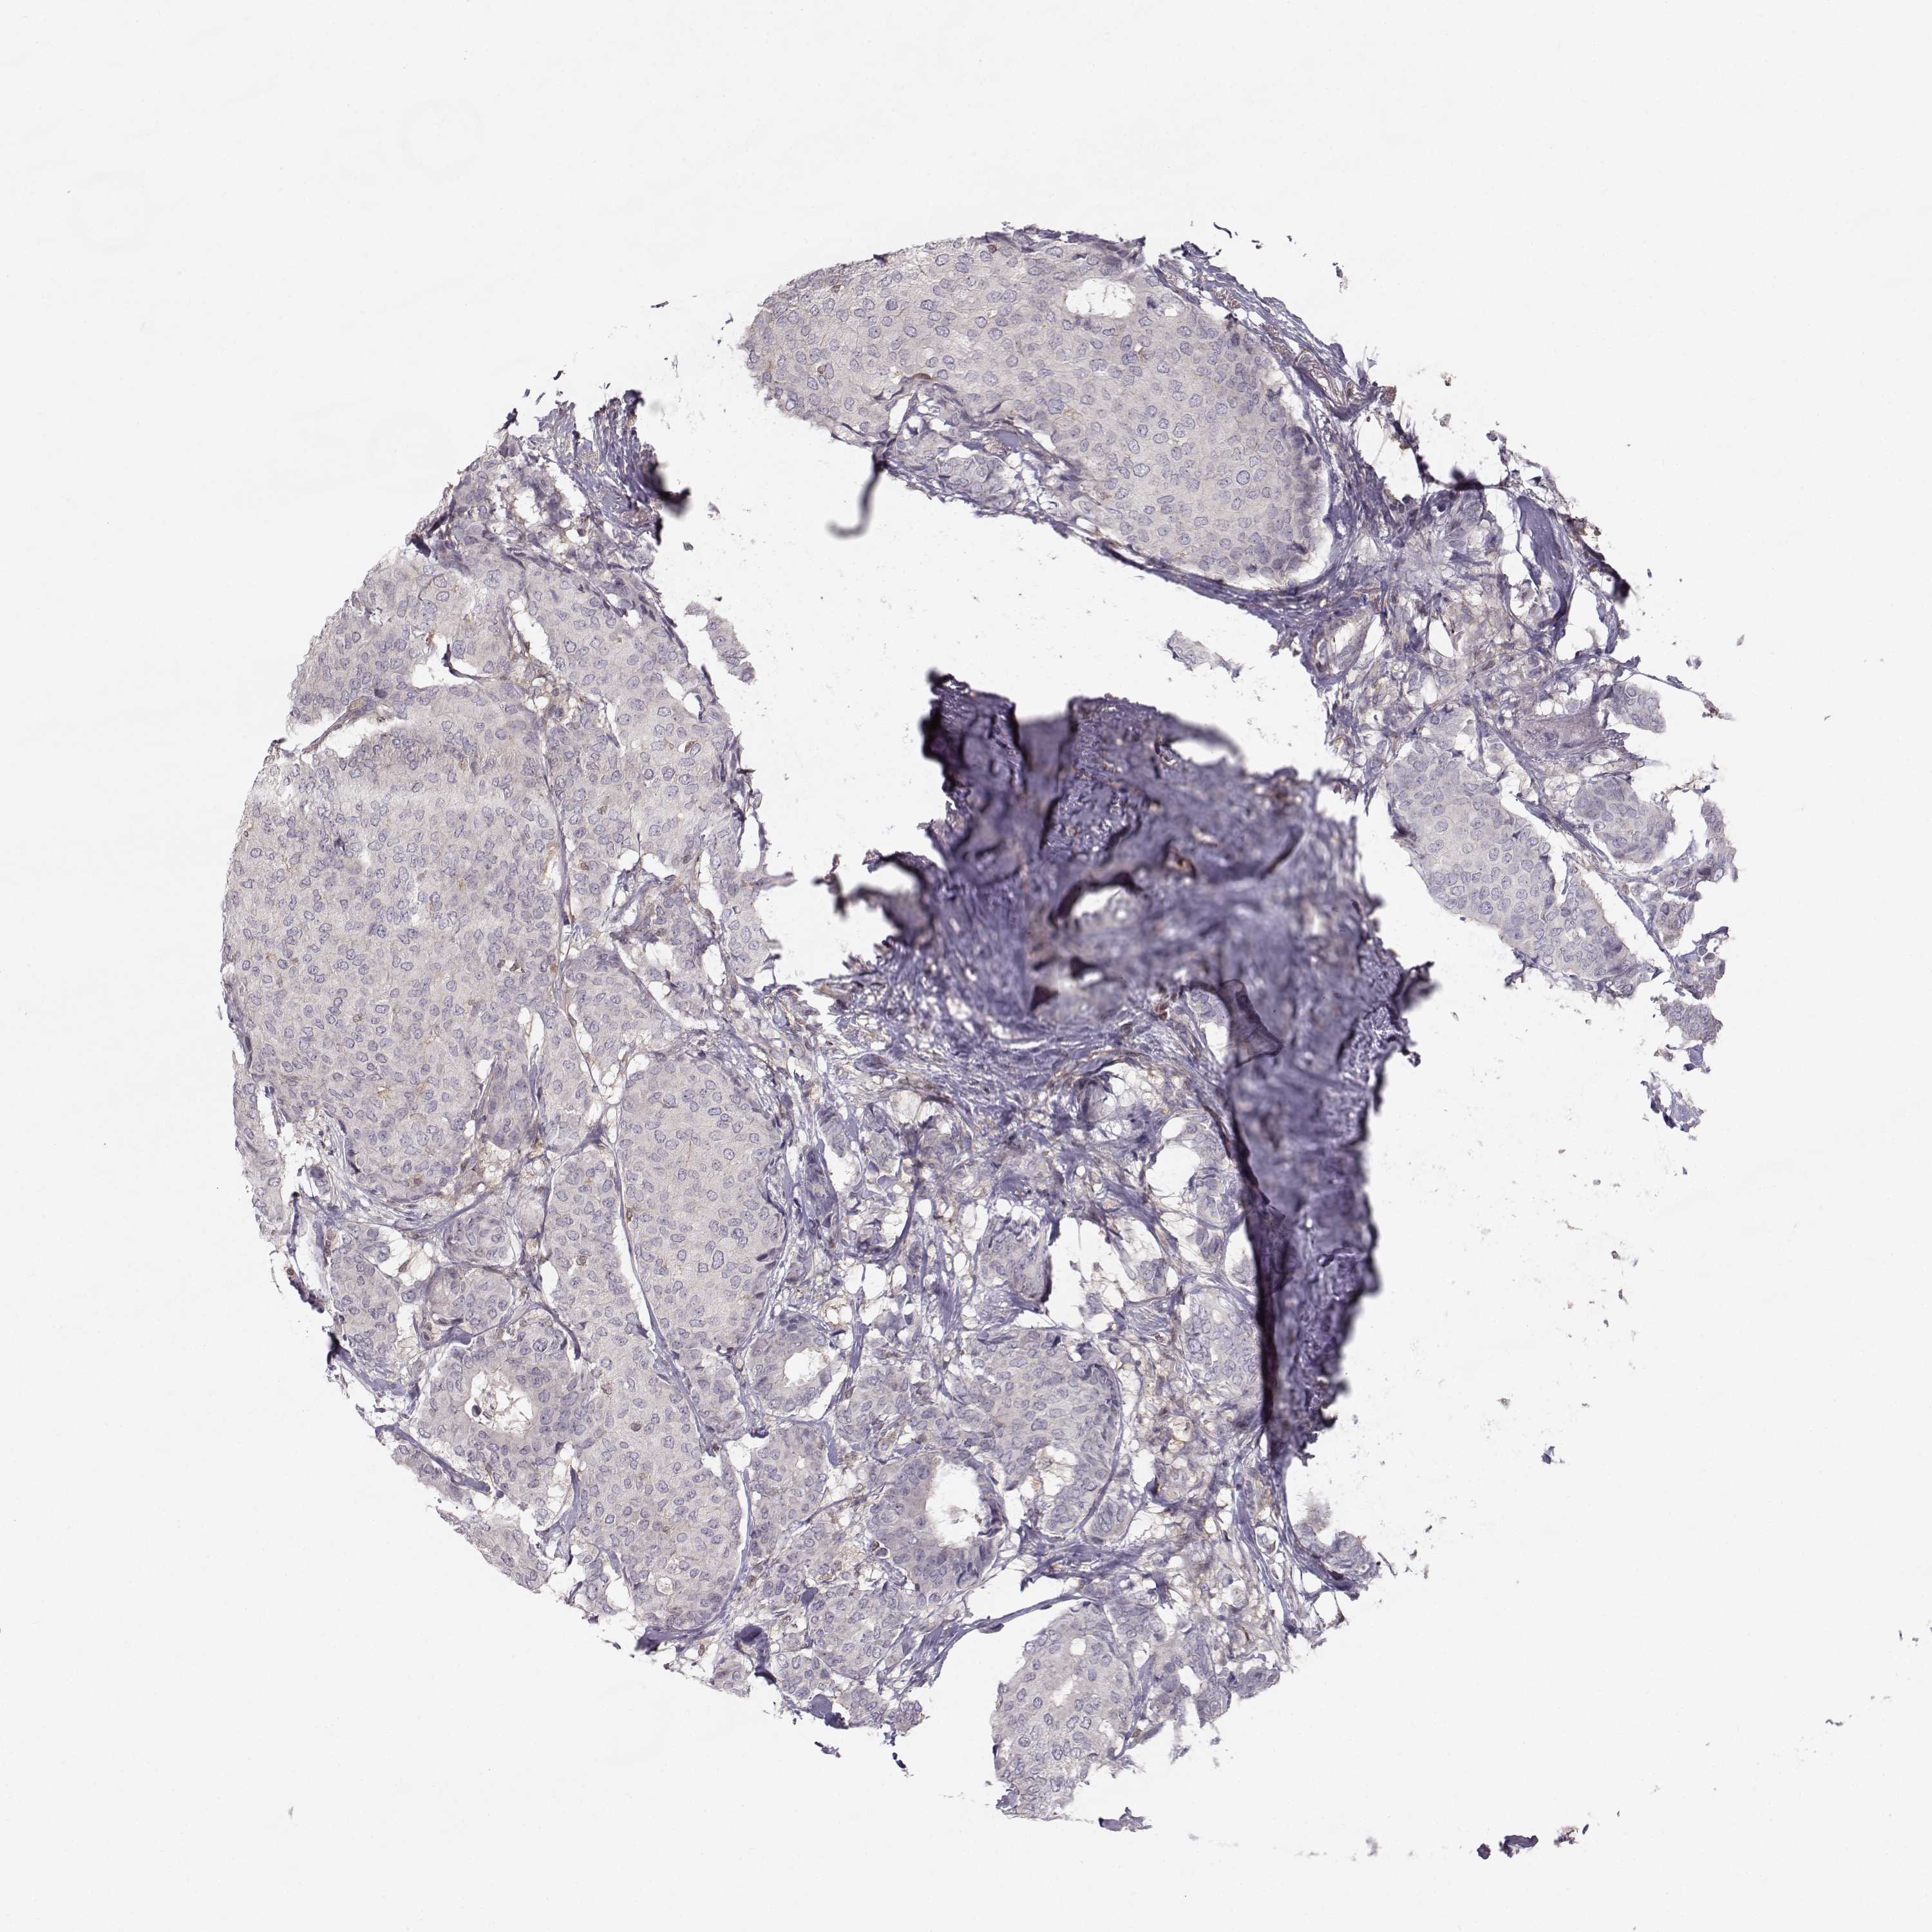

CANCER BREAST CANCER Show tissue menu

BRCA TCGA BRCA VALIDATION PROTEIN EXPRESSION